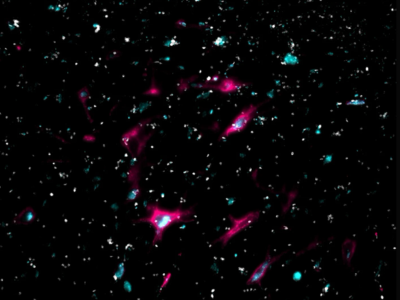

No 5 | Défense immunitaire sur le tissu neuronal